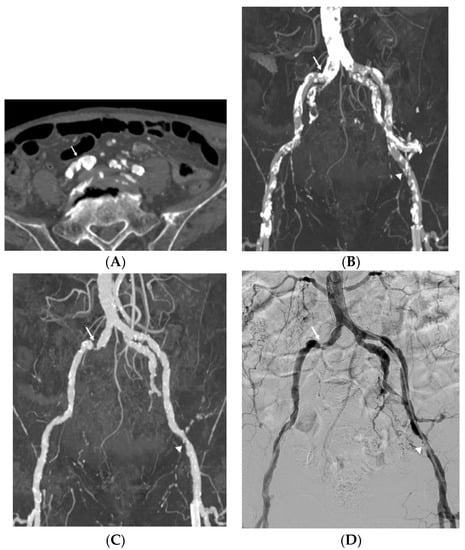

3.1. Image Quality

3.2. Diagnostic Performance

3.3. Impact of Vascular Wall Calcification